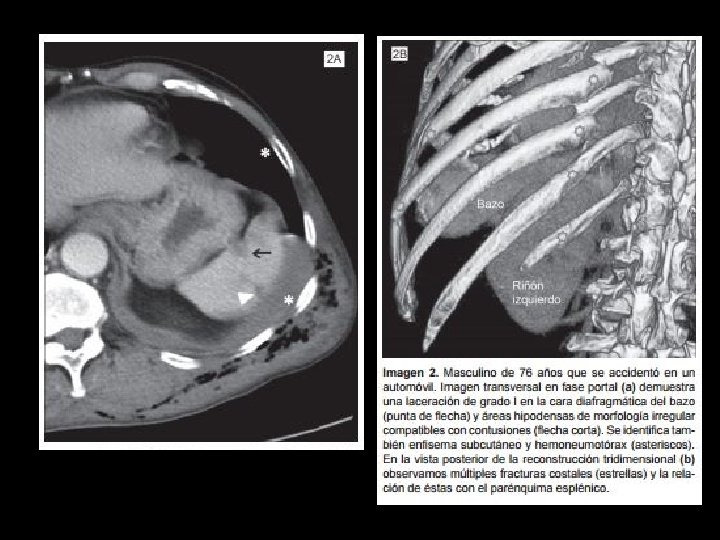

Score de trauma esplénico

Score de trauma esplénico • Tto depende de estadío y del equipo de cirugía:

Score de trauma esplénico • Tto depende de estadío y del equipo de cirugía: manejo qx de II-III por rupturas tardías • Hallazgos de mal pronóstico en manejo no qx: - hemoperitoneo - sangrado activo - grado V